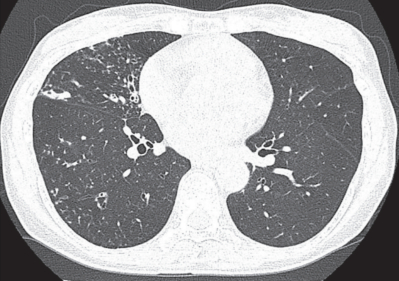

身長 160 cm、体重 44 kg。体温 37.0 ℃。脈拍 80/分、整。血圧 124/72 mmHg。呼吸数 20/分。SpO₂ 98 %(room air)。右前胸部に rhonchi を聴取する。喀痰検査で Ziehl-Neelsen染色が陽性であったが、結核菌 PCR 検査は陰性であった。血液検査で抗 MAC〈Mycobacterium avium complex〉抗体が陽性であった。胸部単純 CTを別に示す。